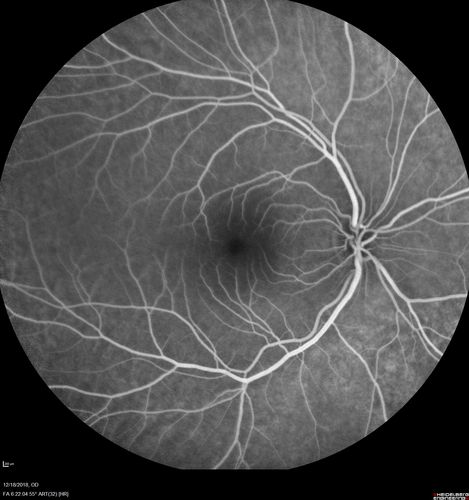

White Retinal Artiole Left eye - Inferotemporal

31 year old female with migraines and headaches for the last 12-13 years. Sometimes she gets the visual symptoms with the migraine. When she gets the migraines the pain is on the left side of her head. She gets the problem a few times a month, sometimes more. They usually last 5-6 hours. She has not had a permanent vision change. When she gets a vision change there are spotty dots of blue neon lights in her vision. With her glasses her two eyes are about the same. VA 20/16 in Each Eye